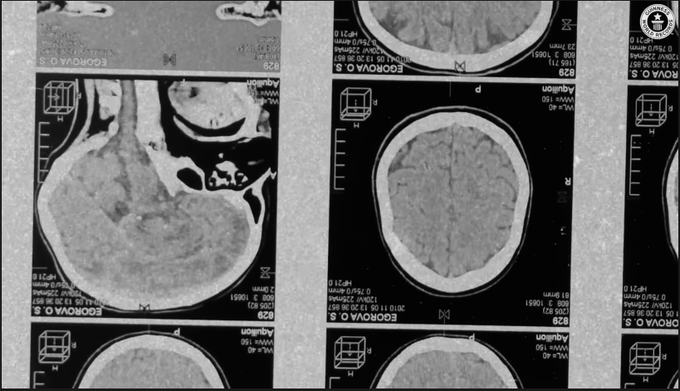

Today, the Guinness World Records *bans* attempts to break Randy’s record

It’s too dangerous

Too unpredictable

Too unethical

Even the military capped their tests at 72 hours

Randy’s 264-hour feat stands *forever* Image